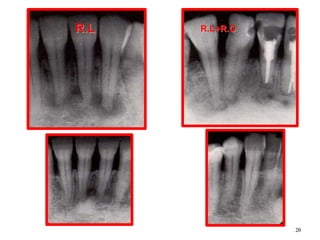

Cementoma

• Usually appears at lower

anterior area.

• First appears as fibrous

tissue stage, which may

confused with a

granuloma (vitality test).

• The second stage is

characterized with

accumulation of calcified

materials.

• The third stage consists of

radio-opaque materials.

Early stage

20

R.L R.L+R.O

21